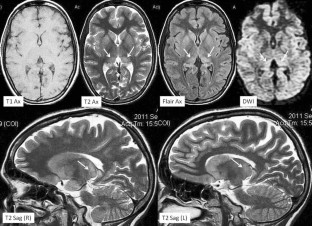

Fig. 2